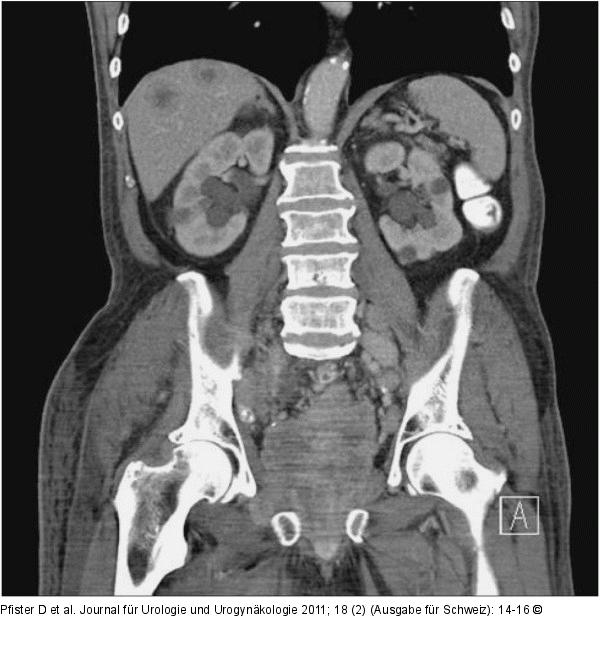

Abbildung 2: Subileus

Subileus mit Harnstauung, Lymphödem und Schmerzen rechtes Bein (Versorgung mit Ureterokutaneostomie bds.) |